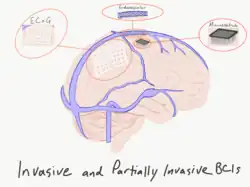

A brain–computer interface (BCI), sometimes called a brain–machine interface (BMI), is a direct communication link between the brain's electrical activity and an external device, most commonly a computer or robotic limb. BCIs are often directed at researching, mapping, assisting, augmenting, or repairing human cognitive or sensory-motor functions.[1] They are often conceptualized as a human–machine interface that skips the intermediary of moving body parts (e.g. hands or feet). BCI implementations range from non-invasive (EEG, MEG, MRI) and partially invasive (ECoG and endovascular) to invasive (microelectrode array), based on how physically close electrodes are to brain tissue.[2]

Partially invasive BCIs

Partially invasive BCI devices are implanted inside the skull but rest outside the brain rather than within the grey matter. They produce higher resolution signals than non-invasive BCIs where the bone tissue of the cranium deflects and deforms signals and have a lower risk of forming scar-tissue in the brain than fully invasive BCIs. Preclinical demonstration of intracortical BCIs from the stroke perilesional cortex has been conducted.[90]

Electrocorticography

Electrocorticography (ECoG) measures brain electrical activity from beneath the skull in a way similar to non-invasive electroencephalography, using electrodes embedded in a thin plastic pad placed above the cortex, beneath the dura mater.[97] ECoG technologies were first trialled in humans in 2004 by Eric Leuthardt and Daniel Moran from Washington University in St. Louis. In a later trial, the researchers enabled a teenage boy to play Space Invaders.[98] This research indicates that control is rapid, requires minimal training, balancing signal fidelity and level of invasiveness.[note 1]